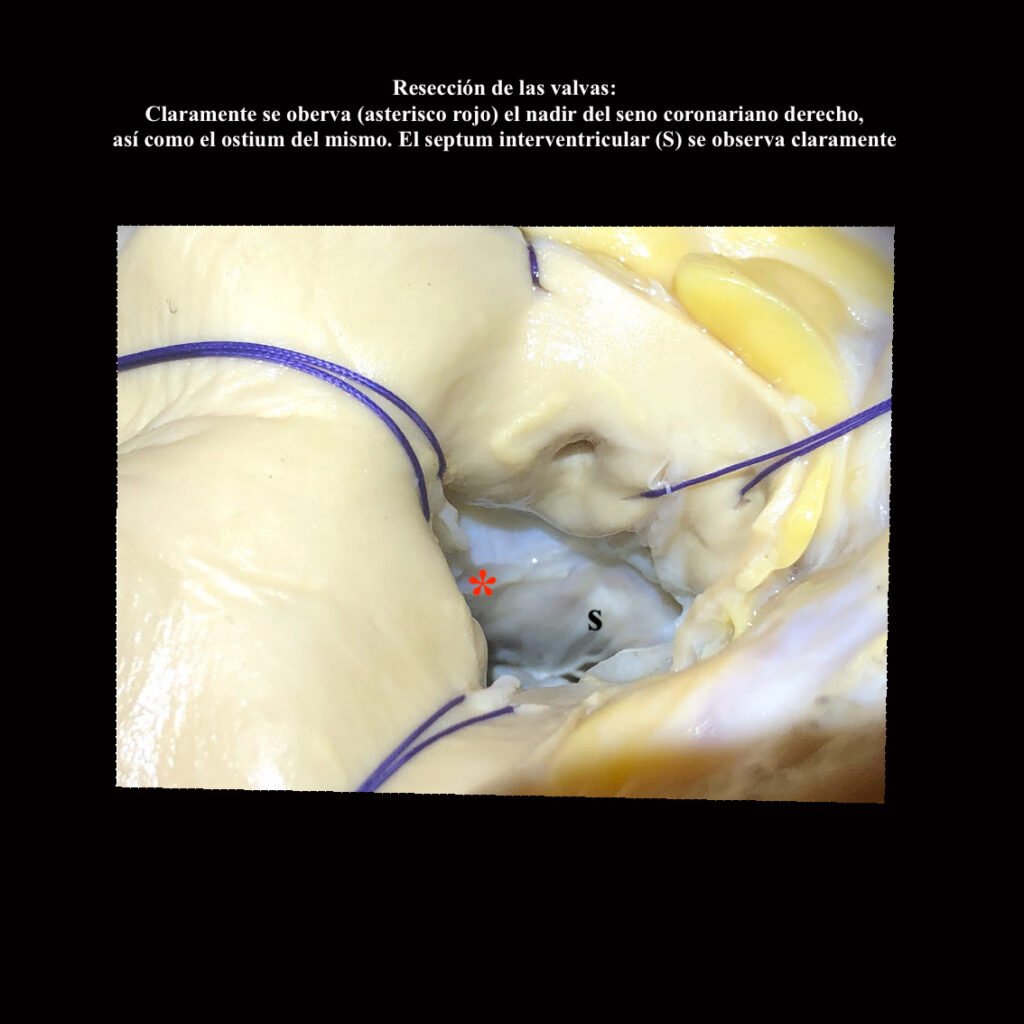

Cirugía que ha resistido el paso del tiempo dado que fue ideada, creada y efectuada en los finales de la década de los ´60 con pocas modificaciones. Mientras dispositivos actuales que cambian en menos de un año prometen milagrosa eficiencia, esta cirugía se ha mantenido y mantiene estables a los pacientes por décadas. Se trata de el reemplazo de válvula aórtica y aorta ascendente con reimplante de los ostia coronarios. En los casos de insuficiencia valvular aórtica y aneurisma de aorta ascendente en donde no es posible salvar la válvula nativa, se realiza este procedimiento sencillo de efectuar si se lo practica unas 100 veces en escenarios de simulación previa.